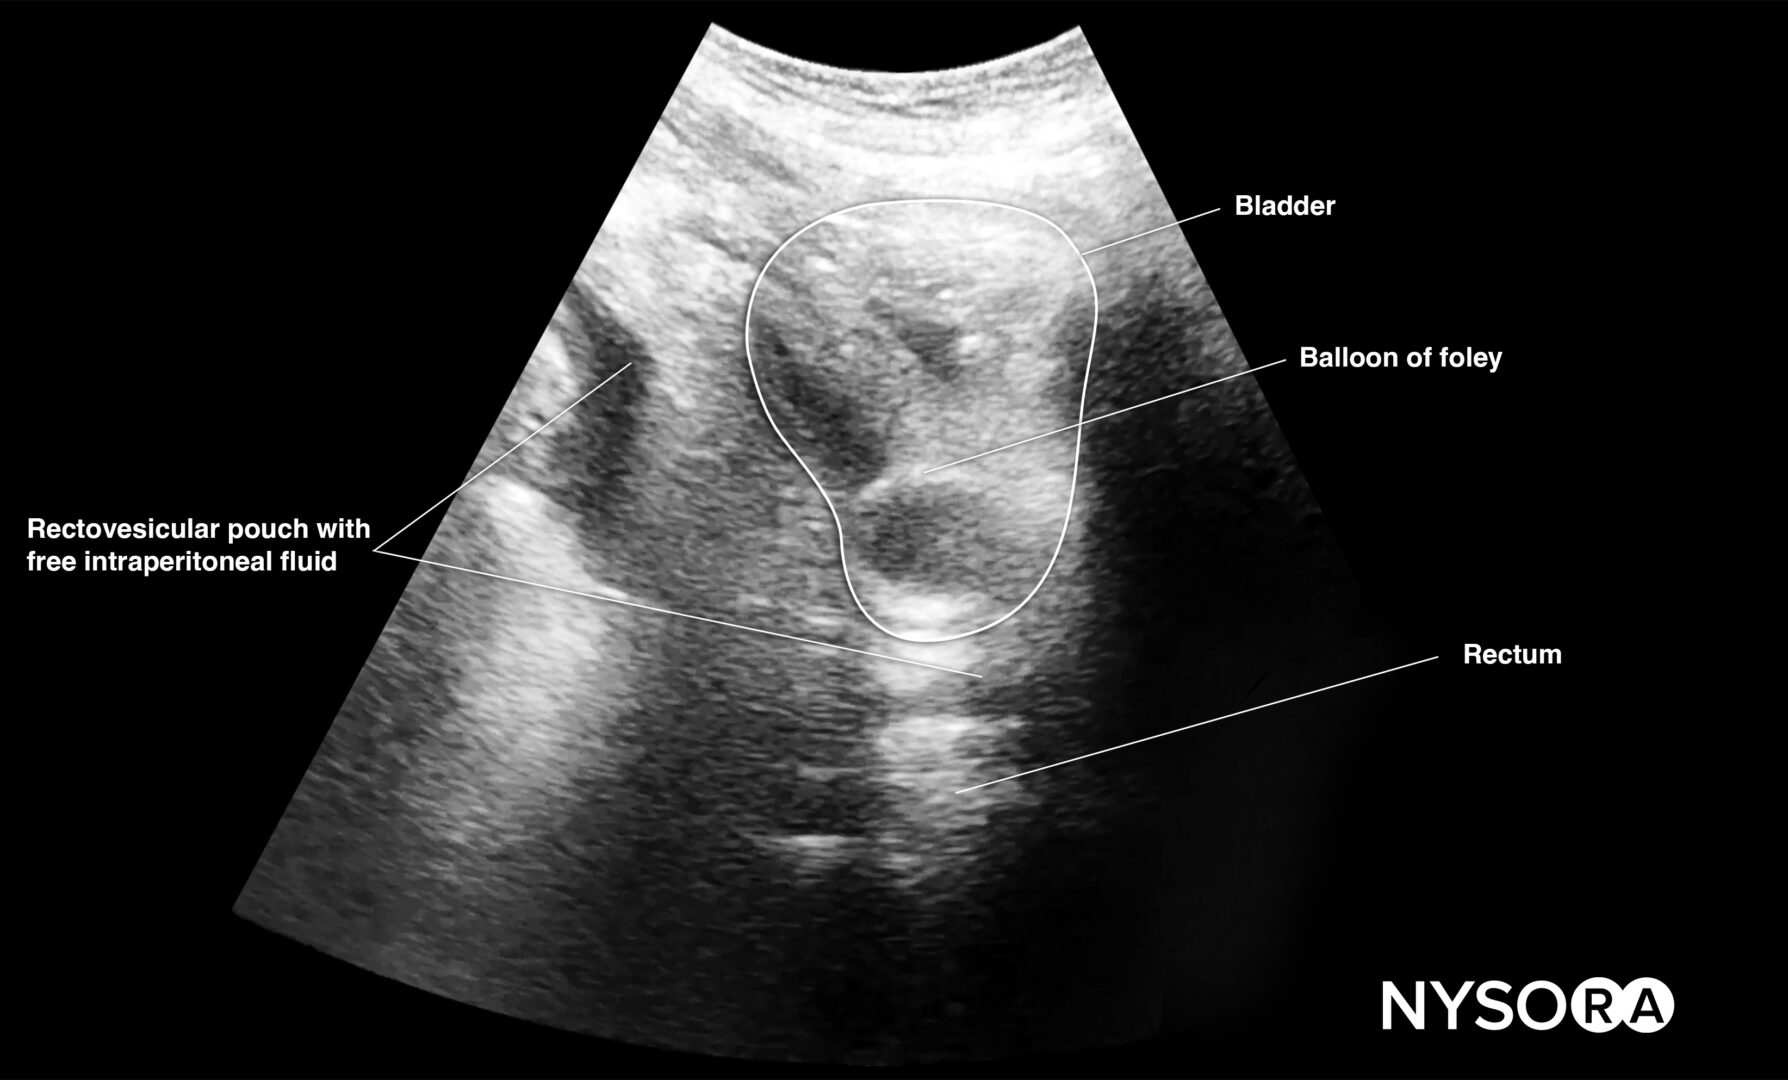

Pelvis

This view assesses the presence of free fluid in the pelvis.

- Position the transducer just above the pubic bone in the midline between the umbilicus and the pubic bone.

- The bladder can be used as an internal anatomical landmark to scan the area behind and lateral to the bladder for free fluid (the rectovesical pouch in men and the rectouterine pouch, or pouch of Douglas, in women).

Pelvic free fluid collects behind the bladder or the area lateral to the bladder (rectovesical pouch in men and the rectouterine pouch or pouch of Douglas in women).

Sonoanatomy of interest in males:

Longitudinal view of the male pelvis with free fluid in the rectovesical pouch after Foley catheter insertion.

Transverse view of the male pelvis with free fluid in the rectovesical pouch after Foley catheter insertion.